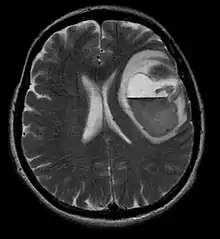

A tomografia computadorizada (TC) e a ressonância magnética (RM) podem detectar efetivamente uma neoplasia no cérebro. A RM é mais sensível que a TC para identificar lesões, mas contraindicações para pacientes com marcapasso cardíaco, próteses incompatíveis, clipes metálicos e outros. A TC continua sendo o método de escolha para detectar calcificações dentro de lesões ou erosões ósseas da calota craniana ou da base. A utilização de agentes de contraste, que são iodados no caso da TC e paramagnéticos ( gadolínio ) no caso da RM, permite a aquisição de informações sobre a vascularização e integridade da barreira hematoencefálica, uma melhor definição do tumor tumoral comparado ao edema circundante e à geração de hipóteses sobre o grau de malignidade . O exame radiológico também permite avaliar os efeitos mecânicos e consequentes alterações nas estruturas cerebrais decorrentes do tumor, como hidrocefalia e hérnias, cujos efeitos podem ser fatais. Finalmente, na preparação para a cirurgia, esse diagnóstico pode ser usado para determinar a localização da lesão ou a infiltração do tumor em áreas vitais do cérebro. Para isso, a RM é mais eficiente que a TC, pois pode fornecer imagens tridimensionais.

As ferramentas de diagnóstico por imagem radiológica destacam a mudança no tecido neoplásico em comparação com o parênquima cerebral normal (através de alterações na densidade do tecido fotografado eletronicamente na TC e na intensidade do sinal na RM). Como a maioria dos tecidos patológicos, os tumores também são reconhecidos por um acúmulo aumentado de água intracelular. Na tomografia computadorizada aparecem hipodensa, ou seja, de menor densidade que o parênquima cerebral, na tomografia de ressonância magnética nuclear com relaxamento spin-lattice T 1 hipointenso e em relaxamento spin-spin T 2 bem como a ponderação de prótons (PD) hiperintensa.

A área saudável do cérebro não deve mostrar nenhuma luminescência específica em uma imagem radiológica. Portanto, nem é preciso dizer que é dada atenção a faixas de sinal de contraste maiores.

No tecido tumoral, em geral, a maior proporção de realce pelo contraste se deve à barreira hemato-tumor particular que permite a passagem de iodo (TC) e gadolínio (RM) para o espaço intersticial extravascular intratumoral. Isso aumenta o sinal (densidade ou intensidade) do tumor. No entanto, deve-se ter cuidado para garantir que o realce do contraste não diferencie definitivamente a neoplasia do edema periferida. De fato, o achado anátomo-patológico no tecido tumoral de glioma infiltrante maligno, como no glioblastoma e no astrocitoma anaplásico, também mostra além do edema vasogênico causado pela destruição da barreira hematoencefálica pelo tumor. Esta última condição clínica é pouco detectável pelo diagnóstico por imagem.

A tomografia computadorizada do cérebro normalmente mostra uma massa de tecido que pode ser realçada por qualquer contraste. Na TC, os gliomas de baixo grau geralmente parecem isodensos ao parênquima normal e, portanto, podem não apresentar realce pelo contraste. Da mesma forma, lesões na fossa posterior do crânio são difíceis de identificar na TC. Consequentemente, os resultados dessa tomografia isoladamente nem sempre são suficientes para fins diagnósticos. Em casos duvidosos, o uso da ressonância magnética mais sensível é essencial.

Na ressonância magnética, um tumor intracraniano aparece como uma lesão maciça que pode se tornar mais luminescente após o uso do agente de contraste. No entanto, há sempre uma anomalia de sinal na ressonância magnética, que indica a presença de neoplasia ou edema vasogênico. Normalmente, o aumento da luminescência (realce pelo contraste) é indicativo de um tumor de grau mais alto de malignidade. Um anel contrastante é característico do glioblastoma, com a porção luminescente correspondendo à parte vital do tumor maligno e a área mais escura-hipointense à necrose tecidual.